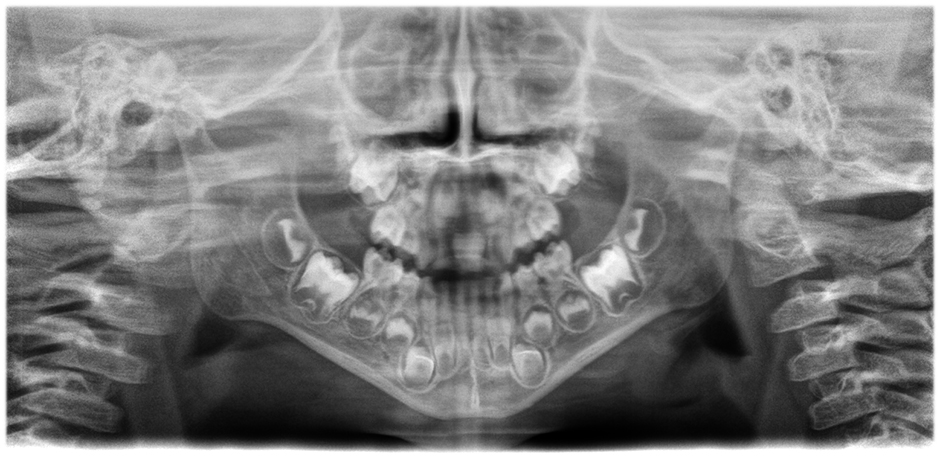

• Panoramiche incredibilmente chiare e definite

grazie ad un sistema di autofocus a 21 strati integrato nella funzione automatica di correzione della posizione del paziente. Scorri le immagini per vedere la differenza (panoramica di sinistra senza, panoramica di destra con autofocus e correzione della posizione del paziente)